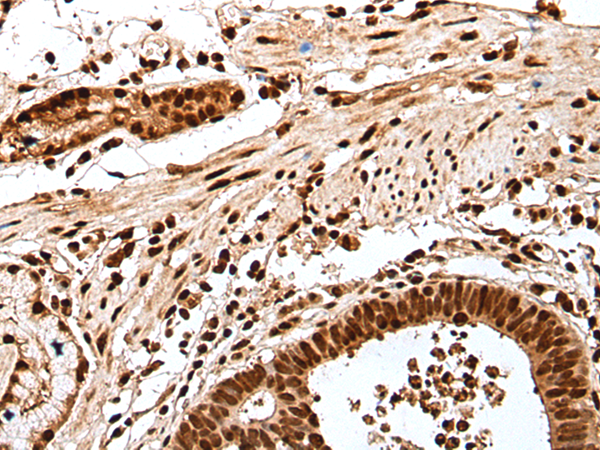

ELISA, IHC |

IHC positive control: |

Human esophagus cancer and human gastric cancer |

IHC Recommend dilution: |

25-100 |